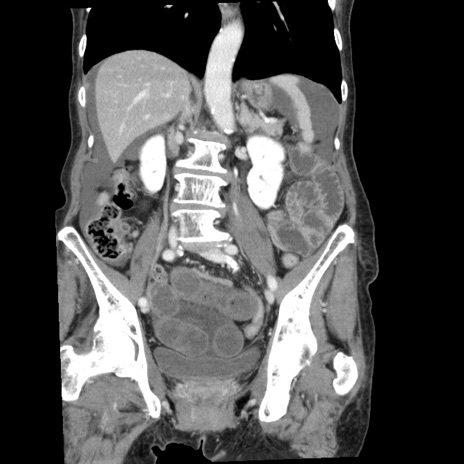

症例1(冠状断像)

【症例】80歳代女性

【主訴】腹痛

【現病歴】8時間前から腹痛あり来院。

【既往歴】糖尿病、脂質異常症、子宮体癌にて子宮全摘術

【身体所見】意識清明・会話良好だが腹痛で苦悶様、全腹部にわたって反跳痛と圧痛あり

【データ】WBC 13600、CRP 0.14、LDH 224、CK 90